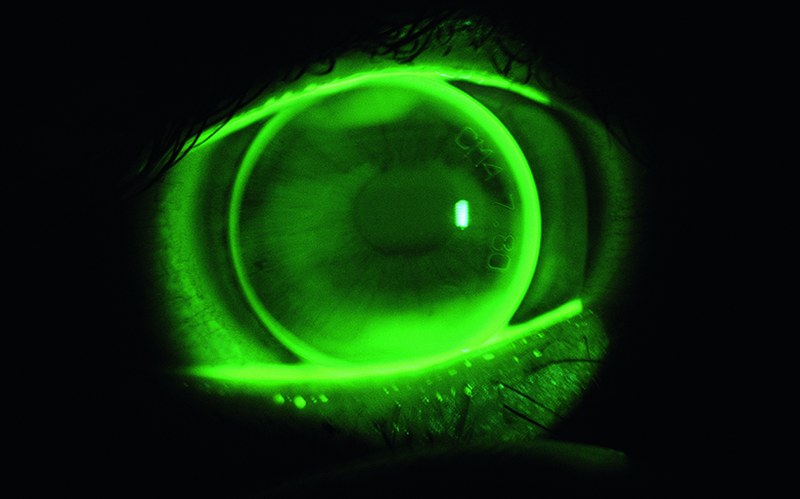

Development of a specialised contact lens with a built in pressure sensor for continuous determination of intraocular pressure.

Glaucoma represents the most common cause for blindness in the western world This eye condition is often associated with increased intraocular pressure. This may fluctuate considerably, particularly in patients with glaucoma. Its continuous measurement may therefore have an important diagnostic impact.

The Institute of Optometry developed the contact lens geometry, enabling the physical intraocular pressure measurement and taking into account physiological compatibility with the eye.